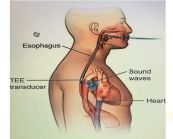

Siêu âm tim là phương pháp chẩn đoán hình ảnh không xâm lấn, an toàn và được sử dụng rất phổ biến trong xác định những bất thường của tim. Dưới đây là hình ảnh mặt cắt quét cạnh ức trái trục ngắn trong siêu âm tim bẩm sinh. Mời các bạn tham khảo!

Tiến hành thăm dò các vị trí mặt cắt cạnh ức giúp đánh giá thất trái, so sánh kích thước các buồng tim và định khu tràn dịch màng tim, phân biệt tràn dịch màng tim và tràn dịch màng phổi. Dưới đây là hình ảnh mặt cắt quét cạnh ức trái trục dài trong siêu âm tim bẩm sinh. Mời các bạn tham khảo!

Tiến hành thăm dò mặt cắt từ mỏm được nhận xét là sẽ khó hơn nhưng kỹ thuật này có tác dụng trong so sánh kích thước buồng thất và là cửa sổ tốt nhất nhằm đánh giá những bất thường về vận động ở vùng vách liên thất và thành tim. Đây là hình ảnh mặt cắt 3 buồng tim từ mỏm trong siêu âm tim bẩm sinh. Mời các bạn tham khảo!